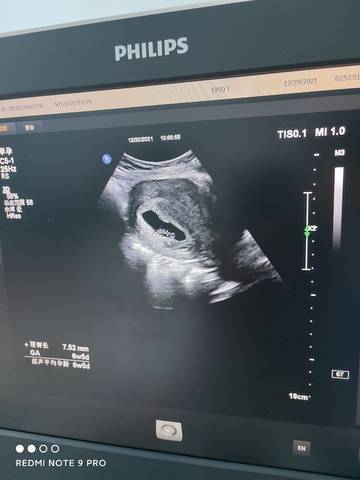

六周五天,胎芽胎心都挺好,就是不知道是男孩女孩,有会看的么?

journal_insert_pic_1683108714journal_insert_pic_1683108768

您好,通过这一个的话是看不出来宝宝性别的,不过这个看的话,孕囊是茄子型的,应该是个男孩子吧?